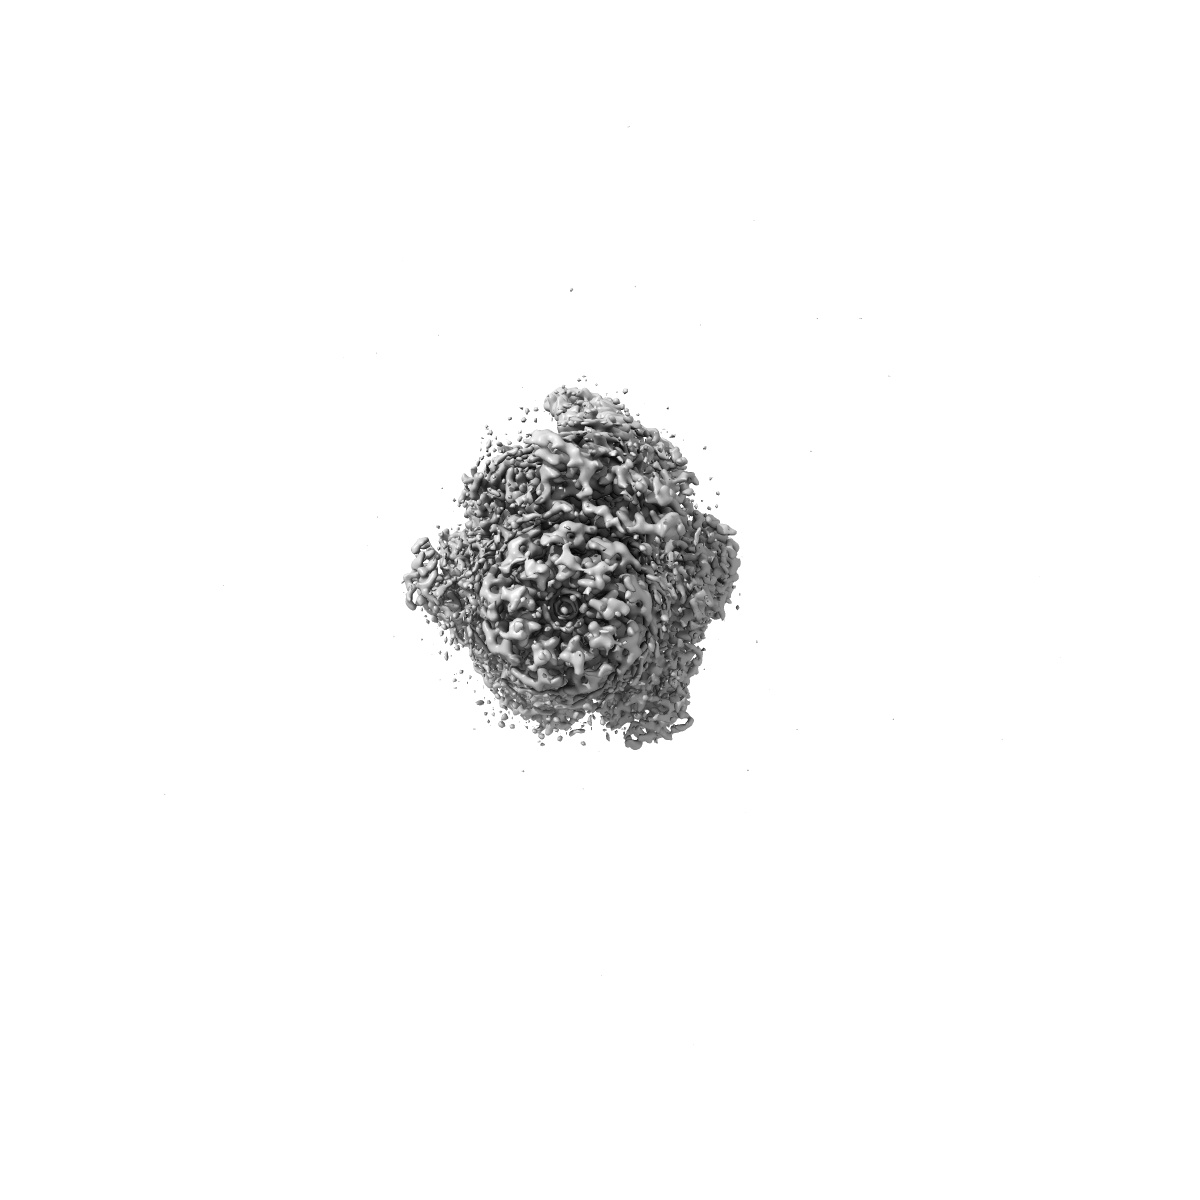

Cryo-EM structure of Mycobacterium tuberculosis ATP synthase in complex with bedaquiline(BDQ)

Single-particle2.58 Å

Sample: Mycobacterium tuberculosis ATP synthase in complex with bedaquiline(BDQ)

Inhibition of M. tuberculosis and human ATP synthase by BDQ and TBAJ-587.

(2024) Nature , 631 , 409 - 414